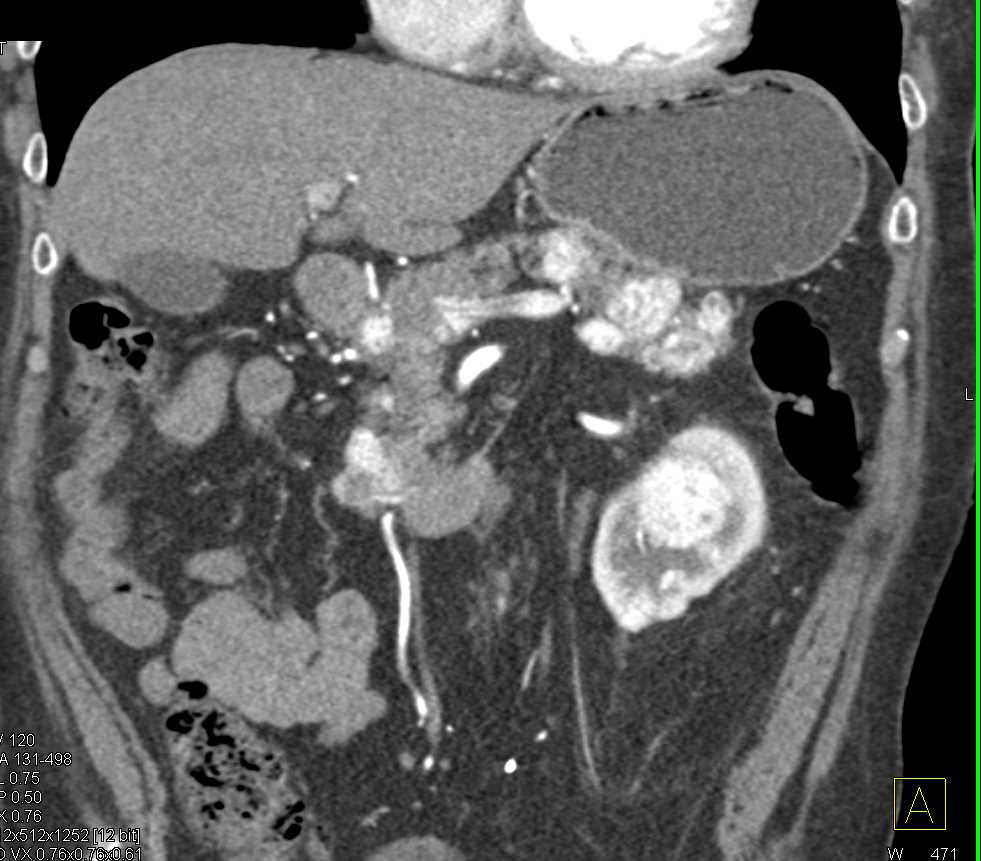

Left Renal Artery Aneurysm